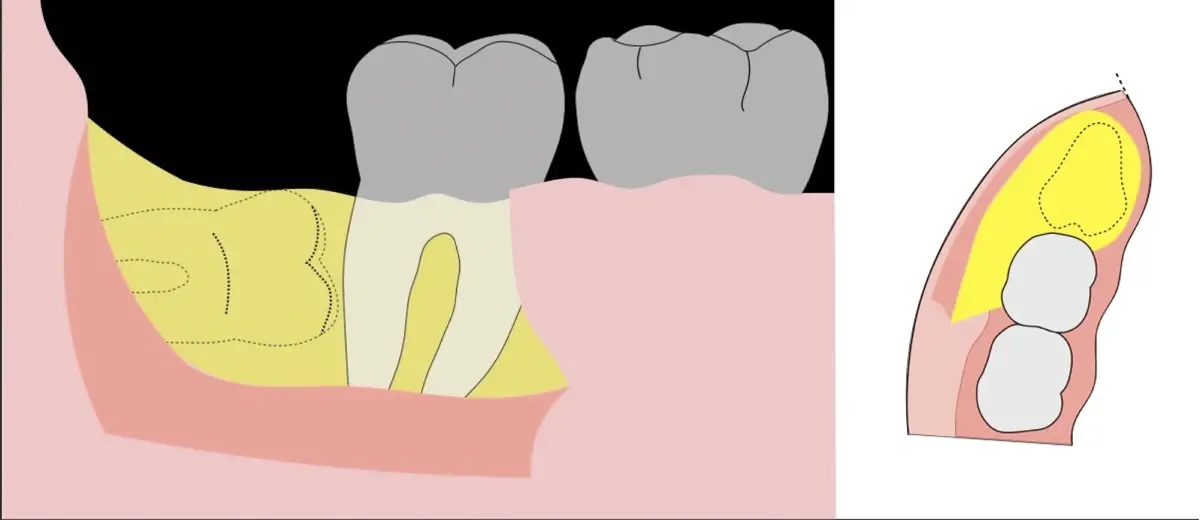

Es imprescindible conocer la ubicación de la tercera molar. Se puede emplear, adicionalmente a la evaluación clínica, herramientas radiográficas (panorámica y periapical) y tomográficas (Cone beam) para determinar la posición, grado de retención y proximidad a estructuras vecinas de riesgo como el nervio dentario inferior y así evitar lesiones (Figura 1).

El procedimiento se inicia colocando anestesia troncular para bloqueo del nervio dentario inferior y sus ramas. Luego, se establecerá el diseño de acceso según la disposición de la molar a extraer. Para fines didácticos, se explicará cómo se realizaría la extracción de la molar de la Figura 1: se realiza una incisión horizontal a nivel de la zona retromolar hasta llegar a distal de la segunda molar, continuándose con una incisión intrasurcular hasta mesial de la segunda molar, finalizando con una incisión vertical a espesor total hasta llegar a la línea mucogingival (Figura 2).